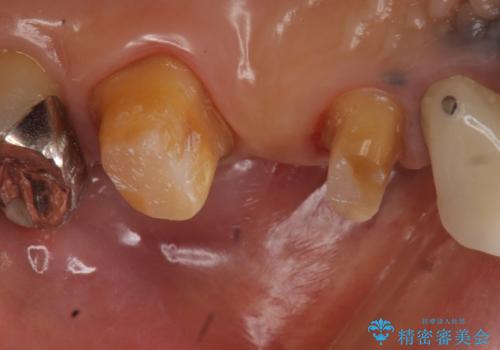

- 昔治療した左上56の延長ブリッジをきちんと治療しなおしたいといらっしゃった方の症例です。

古いブリッジを除去後、オールセラミッククラウンによる補綴を行いました。